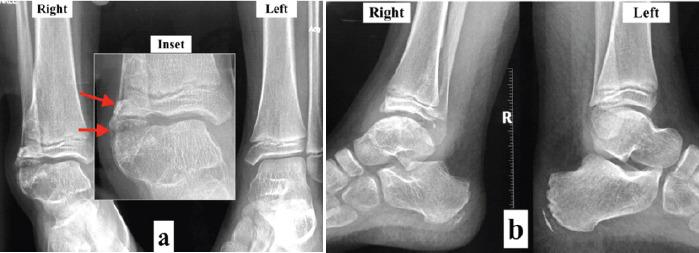

一名9岁男性,在过去1.5年中,右踝背侧外侧出现疼痛性肿胀及足部肿胀。X线片和计算机断层扫描显示胫骨远端外侧骨骺和距骨穹窿部有骨疣形成。骨骼检查发现股骨远端骨骺有软骨性骨疣,确诊为此病。进行了广泛切除,在8个月的随访中,患者无症状且无复发。

骨骺半侧发育不良,又称特雷弗病,是一种儿童罕见的骨骼发育障碍,其特征为儿童期骨骺软骨不对称生长。该疾病在踝关节处可呈局部侵袭性,可导致畸形或不稳定。我们报告一例9岁患者累及胫骨远端外侧和距骨的特雷弗病病例,并重点介绍其临床和放射学表现、治疗及结果。